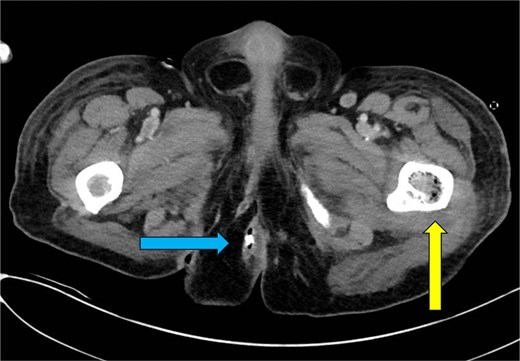

Three weeks later, the patient presented to a rural ED with fevers documented to 103.5°F (39.7°C), intractable low back pain and in severe sepsis. Hemodynamics stabilized following fluid resuscitation. He received vancomycin and meropenem prior to transfer to our facility. There was exquisite tenderness overlying the midline lumbar spine and uninfected, healing granulation tissue overlying previous perianal fistulae. His white blood cell count (WBC) was 26.21, CRP was 42.6 mg/dl (0–0.8 mg/dl) and lactate was 5.2 mmol/l (0.5–2.0 mmol/l) and glucose 99. Blood cultures were negative. CT imaging identified extensive intraosseous gas involving the right pubic ramus, sacrum, bilateral ilia, T6 and T7 vertebral bodies, L1 and L2 vertebral bodies, left proximal femur, sternum, and multiple ribs bilaterally. Soft tissue gas was additionally identified within the right obturator internus and right adductor longus (Figs 2–5). A diagnosis of EOM was made. Daptomycin, cefepime, and metronidazole were started per infectious disease.

CT chest—axial plane. Intraosseous gas visualized in the right sixth rib (yellow arrow, left) and left seventh rib (blue arrow, right).